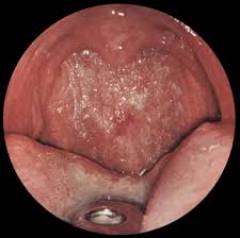

Атрофический вагинит

Симптомы развиваются постепенно:

- Сухость во влагалище — первый сигнал проблемы, возникающий из-за нарушения кровоснабжения стенок влагалища.

- Кровотечения во время интимной близости происходят из-за расположенных близко к слизистой сосудов, которые легко повреждаются.

- Дискомфорт во время полового акта (диспареуния) возникает из-за недостатка кровотока и кислорода, что влияет на состояние стенок влагалища.

- Зуд и жгучая боль появляются из-за истончения и атрофии слизистой влагалища.

- Обильные асептические выделения (в анализе отсутствуют лейкоциты и патогенные микроорганизмы) возникают из-за выхода лимфы, вызванного повреждением мелких лимфатических сосудов, например, во время полового акта.

Степень выраженности симптомов и их наличие зависят от уровня гормональных изменений и частоты обострений заболевания.